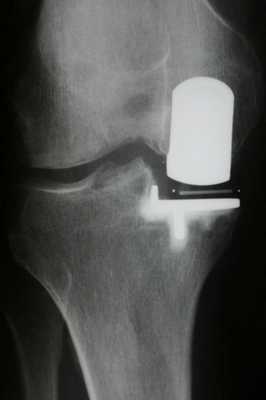

Имплант на рентгене.

Как это выглядит после операции.